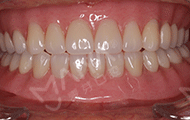

2017年6月 全口种植牙手术成功,感谢麦芽专家团队!

我的牙齿情况比较严重,长期缺牙,不仅缺的数目多,而且骨量出现了萎缩。虽然说麦芽的博士专家团,给我做了all-on-4种植的方案,但还需要结合骨增量来夯实地基。缺牙后提前种牙的好处,就是不会像我一样,出现严重的骨萎缩了。好在麦芽的医生种牙实力很过瘾,我现在四颗钉基本就撑起了半口牙齿,费用真的比单颗单颗种牙,节省了很多!